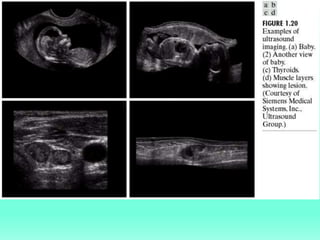

X-Ray images processing, cineangiograms, radiology images

Nuclear magnetic resonance, ultrasonic scanning